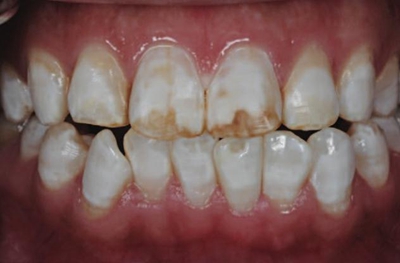

一28歲女性患者來我院修復(fù)科就診,主訴為前牙嚴(yán)重的牙齒著色和缺損十余年,要求改善牙齒的美觀。臨床檢查表明該患者有重度氟斑牙,極大的影響了前牙美學(xué)。

考慮到患者為年輕人,保守治療方法比傳統(tǒng)侵入性治療手段更為合適。術(shù)前牙周治療預(yù)防牙齦炎癥和改善牙齦健康狀態(tài),隨后聯(lián)合采用釉質(zhì)打磨、牙漂白和樹脂滲透來處理牙釉質(zhì)表面。

5、由于氟斑牙存在釉質(zhì)礦化不全等問題,家庭漂白兩周后,使用標(biāo)準(zhǔn)的樹脂滲透技術(shù) (Icon, DMG Products, Hamburg. Germany) 來預(yù)防釉質(zhì)齲。最后,徹底改變患者的前牙美學(xué),并在一年后仍保持穩(wěn)定。